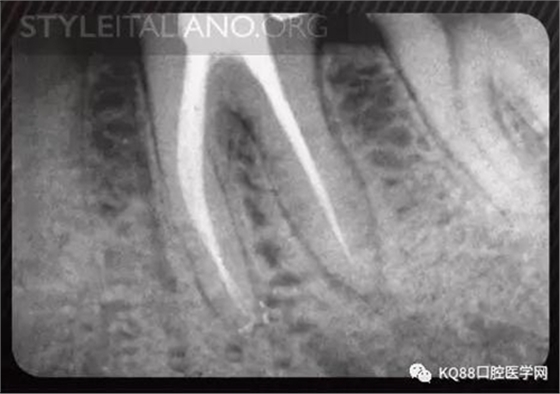

Case 1: In this patient, persistent pain was present after endodontic treatment of a vital tooth. The periapical x-ray showed an inadequate shaping of the distal root canal, regarding both the working length and the apical taper.

Img. 2 - Retreatment of distal canal was performed using ProTaper retreatment files. Working length was assessed electronically. Canal was shaped with a Reciproc R40, thoroughly irrigated with US activation, filled with corresponding Guttafusion obturator. Pain disappeared completely some days after retreatment. In all likelihood, incomplete preparation allowed residual pulp tissue to remain in the root canal, acting as an irritant.